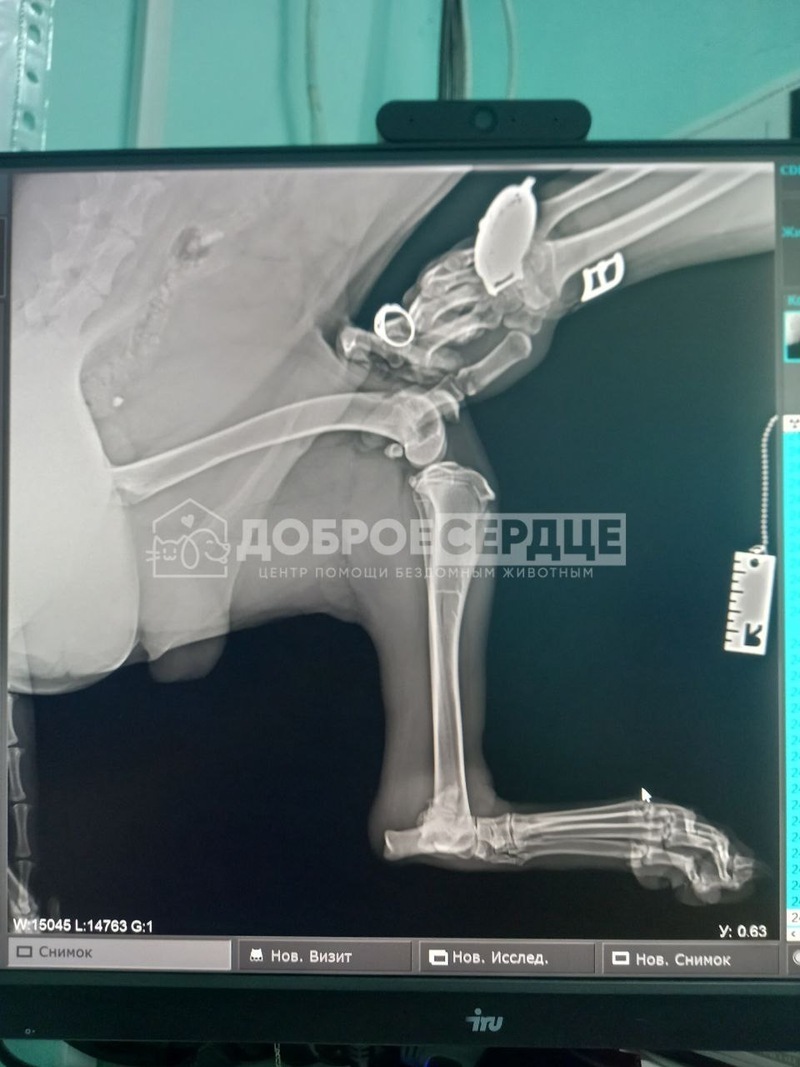

Травму пес Дац получил в пятницу, 29 марта. Диагноз у животного неутешительный — околосуставной перелом правой задней лапы. В Углегорске врачи предложили ампутацию. Однако неравнодушные жители перевезли Даца в Южно-Сахалинск в центр «Доброе сердце».

После осмотра в клинике «Элитвет» специалисты решили взяться за сложную операцию, которая сохранит псу лапу.